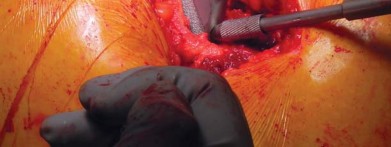

الزرعة نظام Taperloc Microplasty

يفضل الأستاذ الدكتور محمد هطيف استخدام نظام Taperloc® Microplasty من شركة Biomet (وارسو، إنديانا)، وهو أحد الخيارات المتاحة للزرعات الخالية من الأسمنت. يعتمد هذا النظام على تصميم إسفيني مخروطي وسطي-جانبي بدون ياقة، مصمم للتثبيت الذاتي والاستقرار الدوراني.

- المادة والتصميم: مصنوع من التيتانيوم (Ti-6AL-4V) ويتميز بطلاء مسامي رش بلازما محيطي قريب. تستخدم Biomet تقنية خاصة لتطبيق الطلاء المسامي بحيث لا يتم تسخين الزرعة بشكل كبير، مما يحافظ على مستويات عالية من مقاومة الإجهاد.

- الأحجام والتنوع: تتوفر السيقان في أحد عشر حجمًا، تتراوح أطوالها من 95 ملم إلى 130 ملم، وتزداد تدريجيًا جانبيًا بينما يظل الانحناء الأنسي ثابتًا. زاوية عنق-جذع 138 درجة، وهناك خياران للإزاحة: قياسي وجانبي.

- تقنية التحضير: باستثناء موسع الفتحة، لا يتطلب النظام أي كشط؛ فهو نظام يعتمد على التوسيع فقط، مما يسهل الإجراء ويقلل من إزالة العظام.

تحضير الفخذ والحق

يتم تحديد مستوى قطع عنق الفخذ مسبقًا بالتخطيط (باستخدام الأشعة السينية) ومواءمته أثناء الجراحة مع المدور الكبير. بعد قطع عنق الفخذ، يتم تحضير الحُق بالطريقة القياسية قبل تحضير الفخذ. يفضل الأستاذ الدكتور محمد هطيف عادةً وضع الكأس وفقًا للمعالم التشريحية لإعادة إنشاء التوجيه الطبيعي للحُق لدى المريض ويتحقق من الإصدار والميل الصحيحين عن طريق الجس والرؤية المباش